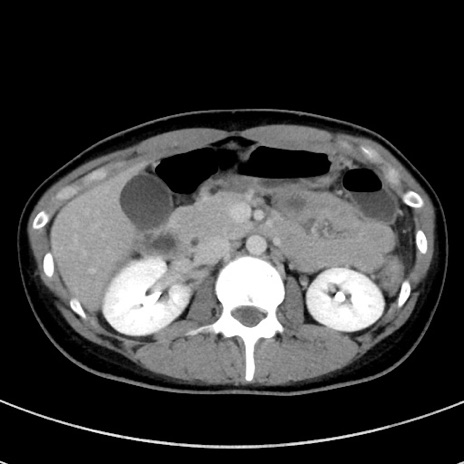

冠状断像

【症例】20歳代女性

【主訴】嘔吐、下腹部痛

【現病歴】昨日夕食後に嘔吐し下腹部痛が出現。本日になっても嘔吐持続し改善しないため来院。

【身体所見】意識清明、BT 37.2℃、BP 108/67mmHg、腹部:平坦、やや硬、下腹部正中から右にかけて圧痛あり、反跳痛軽度あり、tapping pain(+)。

【データ】WBC 13600、CRP 14.94